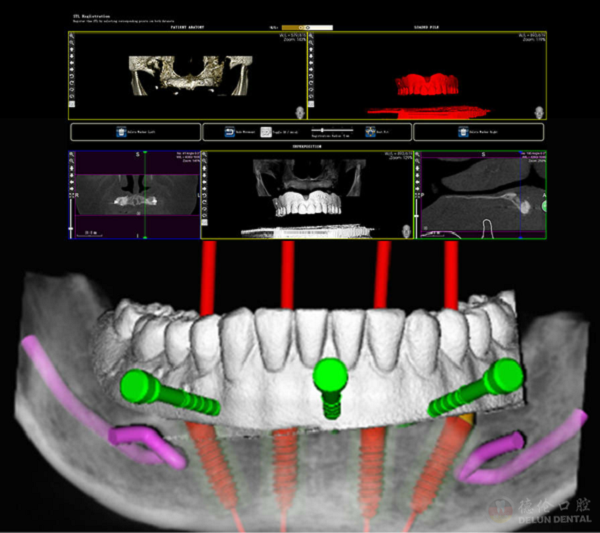

李凯欣介绍,3D数字化舒适种植是医生通过CBCT、口内扫描或者模型口外扫描技术获取到的客户口内详细颌骨及软组织影像信息,在计算机上建成3D数字模型,种植系统软件将血管、神经和上颌窦等植体不能触碰的地方进行呈现,准确判断全口牙床位置,牙床骨深度、厚度及角度,并对颌骨进行观察和测量,同时兼顾后期修复等诸多因素进行综合考虑,医生在进行模拟种植时选择将植体放置在骨量充足、相对可靠的、客户使用更好受力的位置,设计出整套种植方案。由于经过反复的计算机模拟,此时种植体植入位置、轴向和深度是依据颌骨测量结果设计的,进而利用3D打印定制出数字化种植导板。

经过反复的模拟种植,临床手术时减小风险,达到理想种植效果

数字化导板能够帮助医生在种植时实现种植方案所设计的钻头的深度、轴向及位置,从而避免了损伤邻牙牙根、下齿槽神经和不必要的侧穿及上颌窦穿孔;手术中无需翻瓣减少了肿痛和出血量,缩短了种植手术时间,降低了手术感染风险,关键的是增加了可靠性,种植牙也随之得到提高。